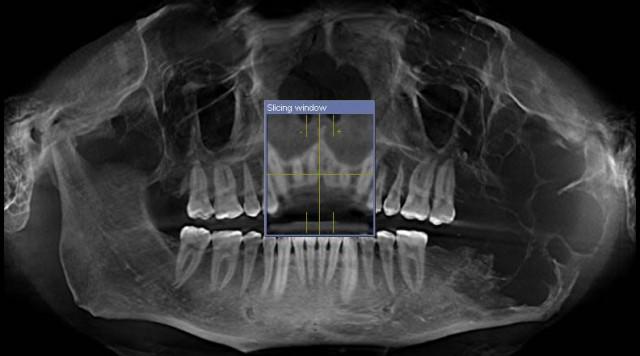

Una imagen de rayos X muestra un gran tumor en el maxilar inferior izquierdo.